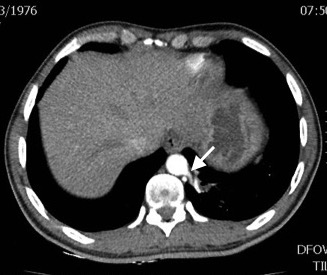

Paciente de 39 años con antecedente de Síndrome de Tolosa Hunt, quien ingresa al servicio de urgencias por disminución de la agudeza visual y cefalea. Dado el antecedente se considera realizar estudios complementarios para descartar enfermedad granulomatosa, como causa del síndrome, encontrando hallazgos incidentales en las imágenes del tórax. El secuestro pulmonar es una anomalía congénita caracterizada por tejido pulmonar displasico, sin conexión normal con la vía aérea, irrigado por la circulación arterial sistémica. Hay dos tipos de secuestros, el intralobar y el extralobar. El intralobar (75%), puede ser congénito o adquirido como secuela de infecciones recurrentes localizadas, está cubierto por pleura del pulmón normal adyacente y generalmente su drenaje venoso es a través del sistema venoso pulmonar ipsilateral. El secuestro extralobar (25%), es considerado una anomalía congénita, está revestido por su propia pleura y su drenaje venoso es sistémico. Tanto el secuestro intralobar como extralobar reciben suplencia arterial sistémica. En los estudios de imágenes, el secuestro se puede presentar como consolidación focal, nódulo o masa, de localización paravertebral, contiguo al hemidiafragma, en los lóbulos inferiores (segmento posterior), con mayor frecuencia en el lado izquierdo (98%) y con una suplencia arterial anómala dada por una o múltiples ramas (15%) generalmente de la aorta torácica y su drenaje puede ser al sistema venoso pulmonar y con menor frecuencia a la circulación sistémica.